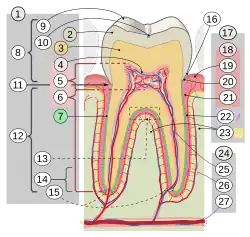

Wurzelform

Eine günstige Wurzelform weisen Zähne mit gespreizten Wurzeln auf, wie sie in der Abbildung an den Molaren zu sehen sind. Ebenso erhöht sich die Pfeilerwertigkeit durch die Form der einzelnen Wurzel, die im günstigen Fall eine zylindrische Form aufweist (in der Abbildung der zweite Zahn von links – Eckzahn 23). Ungünstig sind konisch zulaufende und kurze Wurzeln.